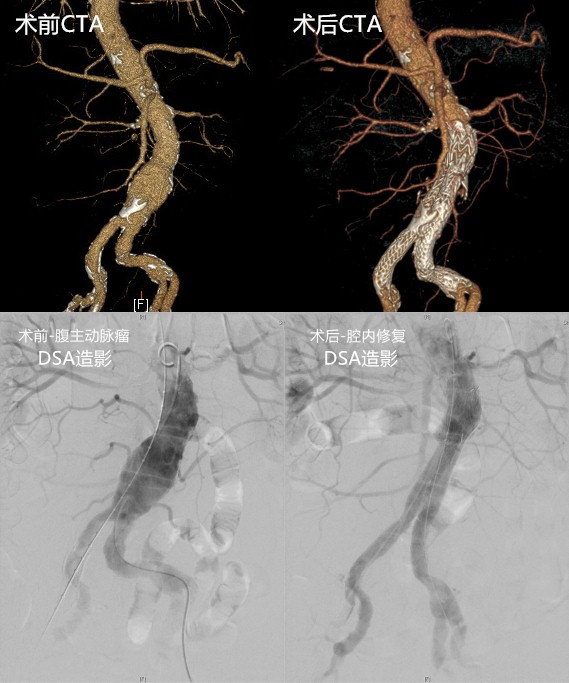

清华长庚医院(通讯员赵传多 杨宇)北京清华长庚医院血管外科联合肝胆外科、麻醉科等相关科室,完成一例同期腹主动脉腔内修复术联合腹腔镜胆囊切除、胆道镜胆管探查术,实现了2种微创技术的珠联璧合。

为此,血管外科专门召集肝胆外科、麻醉科组成多学科会诊小组,为王伯伯设计周密的治疗方案,搭建以吴巍巍主任、麻醉科张欢主任、肝胆外科曾建平教授为核心的治疗团队,敲定同期进行胆道结石与腹主动脉瘤手术。血管外科吴巍巍主任仔细阅片、测量,组织全科讨论,精密制定经皮穿刺腹主动脉覆膜支架植入的腔内治疗方案。麻醉科张欢主任依据患者既往血压控制情况及用药情况,仔细评估麻醉风险,针对可能出现的循环呼吸异常及手术时间较长的困难,谨慎制定多套麻醉预案。肝胆外科曾建平教授术前根据MRCP对患者胆道疾病与胆道走向进行了充分评估,谨防术中胆道损伤,术前指导控制感染,纠正患者水电解质紊乱。

为减少患者手术痛苦及经济负担,三个科室齐心协作,协调心内科、手术室、导管室等多个部门,经过充分的术前准备与麻醉预案,为王伯伯进行了微创腹主动脉瘤支架植入术+腹腔镜胆囊切除及胆总管探查术。术后王伯伯安返病房,恢复顺利,体温明显下降,饮食也恢复了正常,术后第5天就顺利出院。对此,王伯伯深情致谢:能在一次手术同时解决两个问题,既解决了进食后腹痛呕吐的不适,又排除了腹主动脉上的致命威胁,给每一位为我精心付出的医生护士点赞!